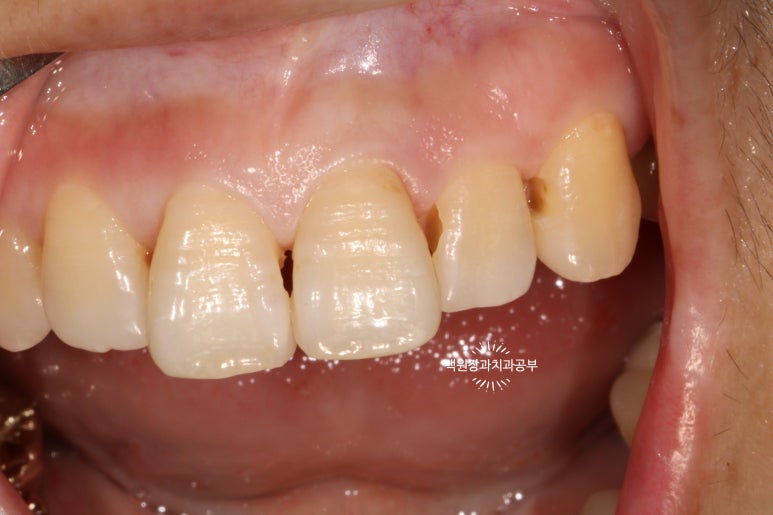

조금 더 제거하고 나니, 이제 치아가 어두워 보이는 느낌이 사라진 것 같습니다.

위 앞니의 뒷면 사진이에요.

치아를 최소한으로 삭제하면서도, 어둡게 썩어있는 부위는 확실히 제거해야 최종 결과가 예쁘게 나온답니다.

위에 보여드렸던 3M 레진을 사용하여 레진충전 완료 후 사진입니다.

3M사의 Filtek Z350 XT Universial 제품과 Filtek Supreme Flowable Restorative 제품을 사용해서 레진충전을 시행하였고, 절단연과 치경부의 색상이 상이하기에 A3, A3.5, OA3 제품을 이용하였습니다.

아까 보았던 것처럼 뒷면에서 바라본 위턱 앞니입니다.

그래서 제 생각에 앞니 레진치료를 잘 하는 사람은 당당히 치아의 뒷면을 보여줄 수 있는 치과의사라 생각해요!

보시면, 거의 색상의 차이나 경계의 구분 없이 자연스럽게 완성된 치아 외형을 관찰할 수 있습니다!